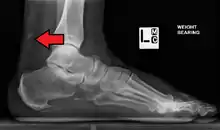

Calcification from dermatomyositis

Magnetic resonance imaging may be useful to guide muscle biopsy and to investigate involvement of internal organs;[14] X-ray may be used to investigate joint involvement and calcifications.[15]